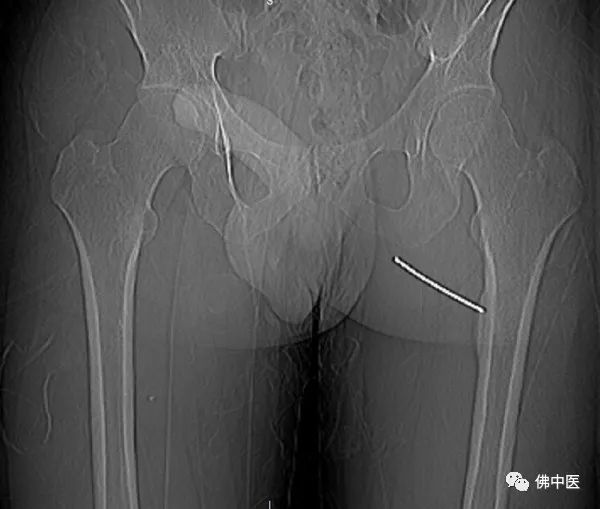

术中,射频针直击病灶

今年1月21日,陈先生与父亲远道而来,找到了劳永锵。据其介绍,陈先生反复左大腿疼痛,疼痛在晚上尤为利害,结合影像学的相关检查,其左股骨上段内侧皮质骨外膜下局灶病变,诊断考虑为骨样骨瘤。